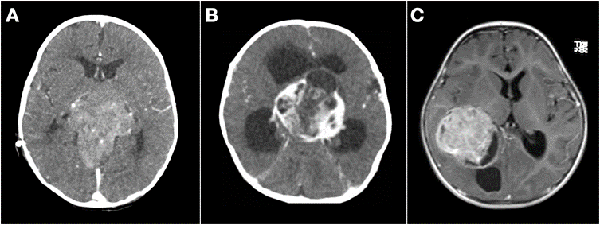

Un tema controvertido es definir cuando un tumor de SNC es congénito. Solitare et al. 14 los divide en: "definitivamente congénitos" que son aquellos que producen síntomas al nacer, "cercanamente congénitos" que son los que producen síntomas dentro de la primera semana de vida, y "probablemente congénito" que son los que se manifiestan dentro del primer mes de vida. La inclusión de pacientes de hasta 2 meses de edad fue propuesta por Arnstein et al. 1 siendo este el límite más aceptado para definir el origen congénito. Sin embargo, hay otros autores como Jellinger y Manoranjan16,17 que extienden esta definición al primer año de vida. Con base en las definiciones de los últimos dos investigadores, nuestra serie presentó 26 casos menores de un año, de los cuales solo 3 fueron menores de 2 meses de vida, todos ellos tumores embrionarios (2 indiferenciados y 1 teratoma inmaduro) (Figuras 2 y 5 B).

Figura 5: Tumores agresivos. A) Paciente de 8 meses de vida, sexo masculino, presentó irritabilidad, macrocefalia y somnolencia. TC de cerebro con contraste EV donde se observó imagen en región pineal que se extiende al tercer ventrículo. Se realizó cirugía de exploración, exéresis parcial, anatomía patológica informó pineoblastoma, paciente falleció a los 5 meses por progresión de la enfermedad. B) Paciente de 2 meses de vida, sexo masculino, consultó por deterioro progresivo del sensorio. TC de cerebro con contraste EV que evidenció lesión centroencefálica e hidrocefalia obstructiva. Se realizó cirugía de exploración de lesión, con colocación intraquirúrgica de drenaje ventricular al exterior. Anatomía patológica informó tumor embrionario indiferenciado. Paciente falleció a los 14 días por progresión de enfermedad. C) Paciente de 19 meses de vida, sexo femenino, consultó por vómitos a repetición. IRM de cerebro con contraste EV que mostró tumor supratentorial intraventricular con realce homogéneo con el contraste EV. Se realizó cirugía de exploración, con exéresis parcial por el intenso sangrado. Anatomía patológica informó carcinoma de plexos coroideos. Paciente fallece a los 3 meses.